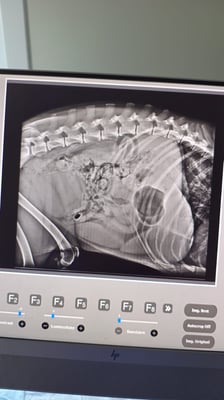

Doch dann erkannte unsere liebe Grig endlich die Ursache für ihren schlechten Zustand: Das arme Mädchen war voller Herzwürmer! Ein Röntgenbild und eine Ultraschallaufnahme zeigten das wahre Ausmaß der Situation.

But then our dear Grig finally recognized the cause of her terrible condition: the poor girl was full of heartworms! An x-ray and an ultrasound showed the true extent of the situation.